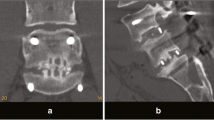

Clinical analysis was performed based on the visual analogue scale (VAS) for radicular pain, Oswestry disability index (ODI) measured 2 weeks prior to and after the operation and at the final follow-up. Two orthopedic surgeons performed radiologic assessment by evaluating the bone fusion for each subject using the 2-year-old standing lateral flexion–extension radiographs and lumbar CT images. And their evaluations were compiled to calculate the mean value using the classification method described by Burkus et al. study (Table 2) [14]. Based on the radiographs, we defined the range of intervertebral motion at 3° or lower, vertebral body displacement of less than 3 mm, and continued formation of trabecular or new bone inside or outside the cage as bone fusion. The level of bone fusion was classified into four grades: Grade I (definitely solid), II (possibly solid), III (probably not solid), IV (definitely not solid). Only Grades I and II were regarded as bone fusion.

Of the 88 subjects, 77 had a bone fusion with a fusion rate of 87.5 %, and 11 did not have the bone fusion (Fig. 2, 3). The radiographs of 11 non-fusion subjects revealed no postoperative complications, including segment instability, dislocation of the implants trials and cage and screw-related complications. Revision surgery was therefore not performed.

The bone fusion rate was 90.9 % in Group I with 100 % autograft, 87.8 % in Group II with over 50 % autograft and 85.7 % in Group III with less than 50 % autograft; however, the differences between groups were not statistically significant (p = 0.22) (Table 4). However, bone fusion exhibited significant differences between graft volume-based groups showing 81.5 % in Group A with less than 12 ml of bone graft and 92.0 % in group B with over 12 ml (p = 0.03) (Table 5).